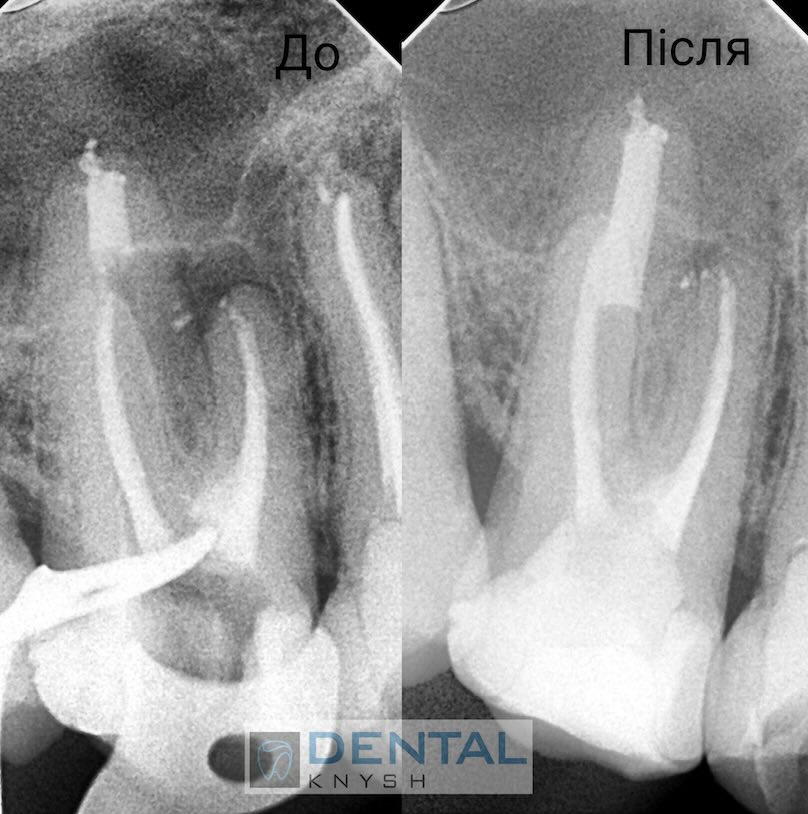

Endodonta Dmitry Kushinsky specjalizuje się w leczeniu kanałów zębowych pod mikroskopem. Ma ponad 8 lat doświadczenia. Wykształcenie: Danylo Halytskyi Lviv National Medical University.

„Leczenie kanałowe pod mikroskopem daje najlepsze wyniki leczenia bez żadnych zastrzeżeń.

Nie każda klinika ma mikroskop do leczenia stomatologicznego, ale w przyszłości mikroskop będzie koniecznością. Im lepszy widok pola pracy, tym lepsze wyniki leczenia.

Początkowo fotele dentystyczne były w tym celu uzupełniane lampami, ale wraz z pojawieniem się mikroskopów stomatologia weszła w nowy etap rozwoju”.

Fotorelacje